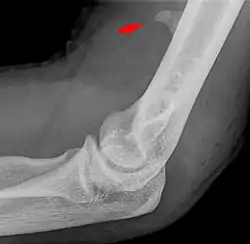

![]() Small supracondylar process seen on a lateral radiograph of the elbow | |

The supracondylar process of the humerus (also known as an avian spur) is a variant bony projection on the anteromedial aspect of the upper arm bone (humerus), about 5–6 cm above the medial epicondyle.[1] It is directed downward, forward and medially pointing to the medial epicondyle. A fibrous band, Struthers ligament, may connect this process to the medial epicondyle.[2] This variation has a prevalence of 0.68% and is significantly more common in women than in men.[3]